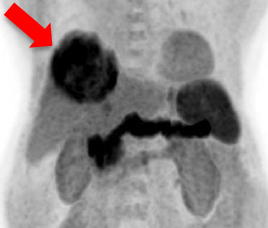

双示踪剂正电子/电脑双融扫描 (C-11 Acetate 及 F-18 FDG) 和 肝细胞癌 钇 90选择性内部放射治疗

- 治疗前双示踪剂正电子/电脑双融扫描

- 识别代谢异质性因子

- 分类细胞分化

- 划定辐射敏感性

- 肝脏肿瘤因代谢高丶体积大而不适宜手术治疗

- 甲胎蛋白水平是2269 ng/ml

C-11 Acetate F-18 FDG